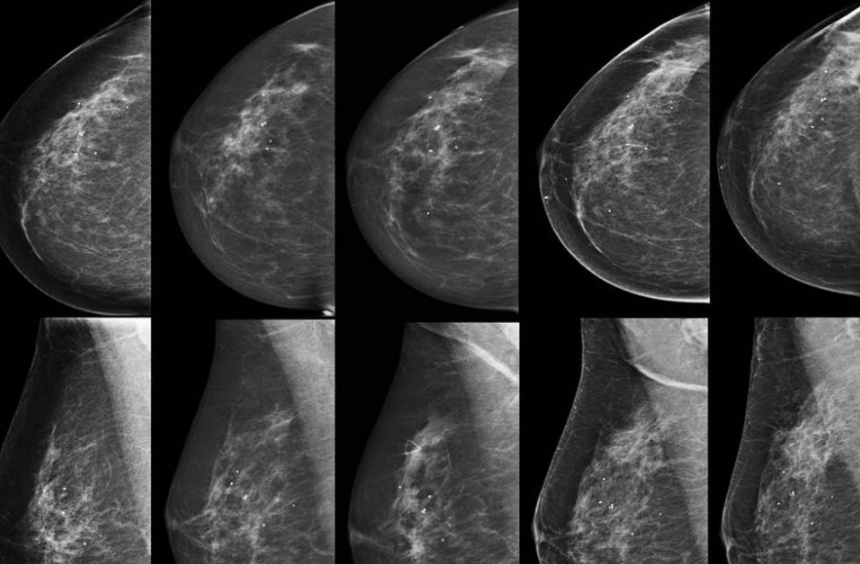

سلول های سرطانی پستان معمولاً توموری را تشکیل می دهند که به واسطه تصویربرداری دیده شده یا به شکل توده احساس می شود.

وی بیان کرد: خودارزیابی پستان و معاینات دورهای غربالگری بهترین راه تشخیص سرطان پستان است و آگاهی از اینکه سینه ها در حالت عادی، چگونه باید باشند، بخش مهمی از بهداشت سلامت پستان است.

این کارشناس افزود: تمامی زنان ۴۰ سال و بالاتر لازم است هر ۲ سال یکبار ماموگرافی انجام دهند، اما در افرادی که سابقه سرطان تخمدان و یا سرطان پستان در یک پستان را دارند و یا سابقه خانوادگی سرطان پستان، تخمدان، پروستات و لوزالمعده دارند، حتما باید غربالگری زودتر انجام شود.